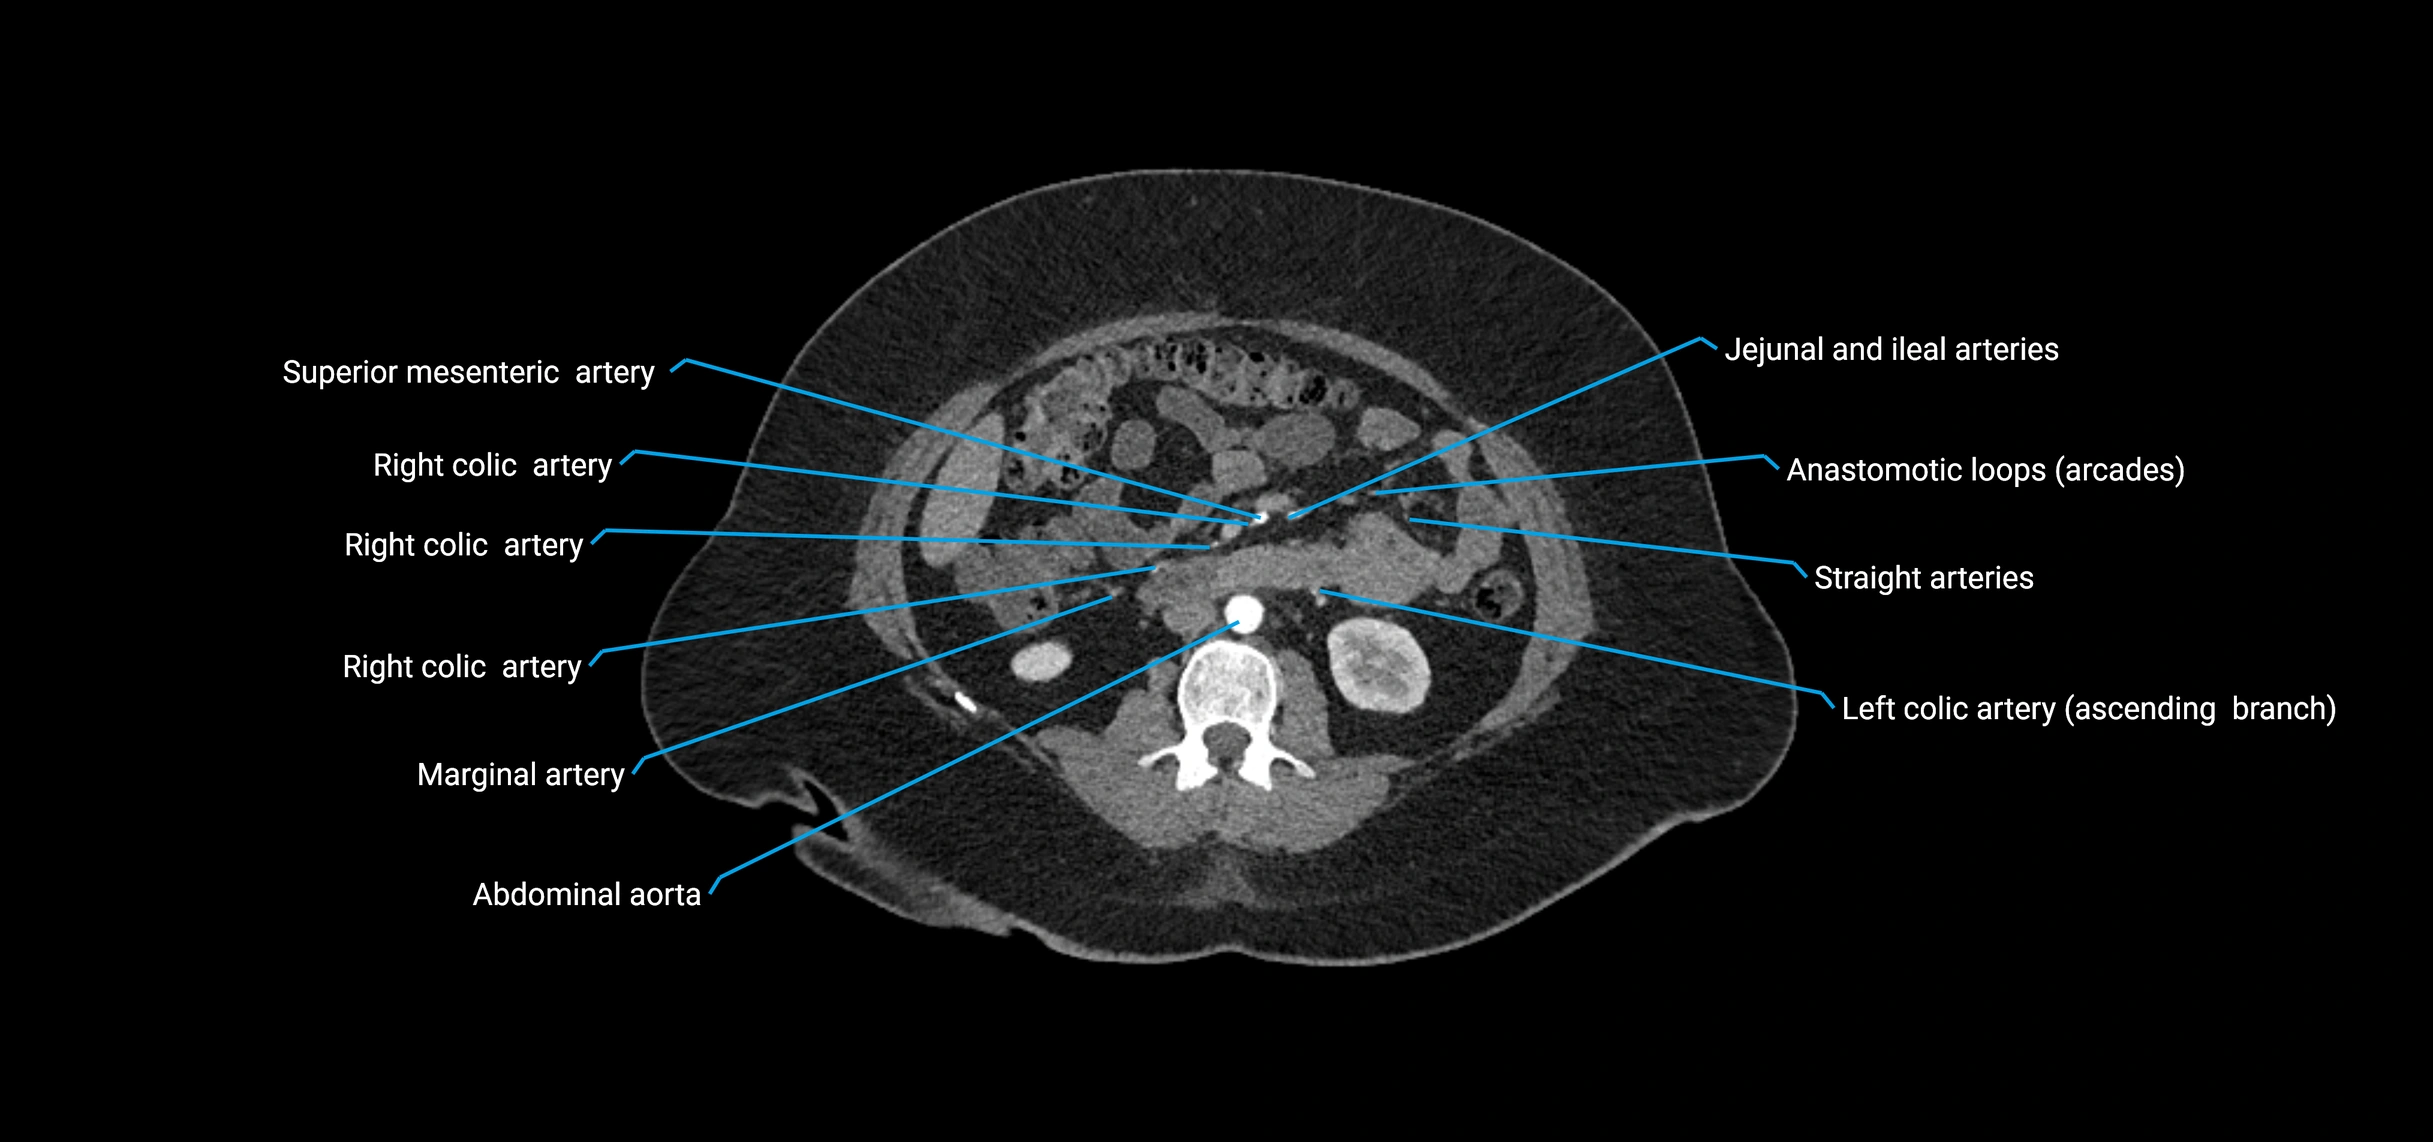

CT images

image